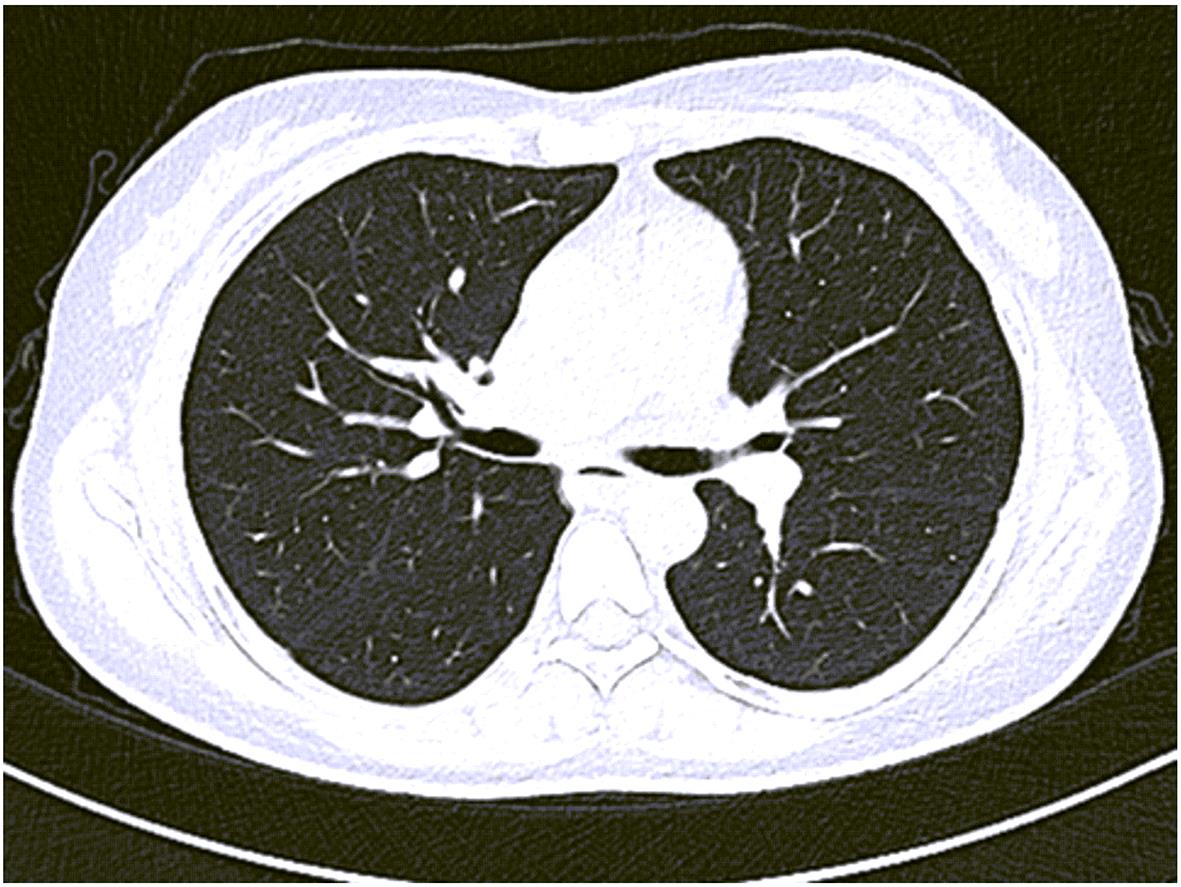

Misdiagnosis of intrapancreatic accessory spleen: A report of two cases

Mengzhe ZHANG, Jie RAO, Zhengle ZHANG

2024, 40(2): 365-368. DOI: 10.12449/JCH240223

Abstract(1274) HTML (315) PDF (1188KB)(59)

Abstract:

Accessory spleen refers to the spleen tissue that exists outside of the normal spleen, with a similar structure to the main spleen and certain functions. Intrapancreatic accessory spleen (IPAS) completely enveloped by the pancreas has an incidence rate of only 2%, and it is easily misdiagnosed in clinical practice due to its atypical clinical symptoms and similar radiological features to pancreatic neuroendocrine tumor, pancreatic solid pseudopapillary tumor, and other pancreatic space-occupying lesions. This article reports the clinical data of two patients with IPAS who were misdiagnosed as pancreatic neuroendocrine tumor and pancreatic solid pseudopapillary tumor, respectively, analyzes the reasons for misdiagnosis, and summarizes the experience in diagnosis and treatment, in order to improve the ability for the differential diagnosis of IPAS in clinical practice.